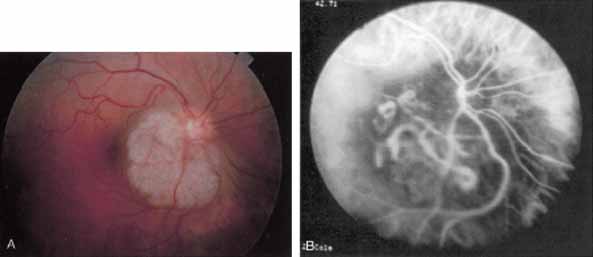

More recently, ICG angiography has begun to play an important role in the management of patients with occult CNV. In particular, the identification and management of two subsets of occult CNV, namely retinal angiomatous proliferation (RAP)34 and polypoidal choroidal neovascularization (PCV),35 are greatly enhanced with ICG angiography. RAP is a distinct subgroup of neovascular AMD in which angiomatous proliferation within the retina is the first manifestation of the process of neovascularization. As the neovascularization proliferates into the outer retina and subretinal space, the angiomatous proliferation is then surrounded by dilated retinal vessels, hemorrhages (preretinal, intraretinal, and subretinal), and exudates. One or more of the related, compensatory retinal vessels perfuse and drain the neovascularization, occasionally forming a retinal–retinal anastomosis (RRA). In these patients, the same indistinct staining seen in occult CNV is present on a fluorescein angiogram. Therefore, most cases of RAP require the use of ICG angiography to make the diagnosis (Fig. 11).34

ICG angiograms of RAP lesions reveal a focal area of intense hyperfluorescence corresponding to a so-called hot-spot of neovascularization with some late extension of the leakage within the retina caused by intraretinal neovascularization (IRN) within the deep layers of the retina. As the IRN progresses down into the subretinal space, the neovascularization present in the choroid joins the IRN to form a large, neovascular complex. At this stage, clinical and angiographic evidence of a vascularized PED (V-PED) is often present. ICG is the preferred method of imaging a V-PED because the serous component of the PED remains hypofluorescent while the vascular component displays hyperfluorescence. ICG angiography may be able to capture direct communication between the retinal and choroidal component of the neovascular complex as they meet to form a retinal choroidal anastomosis (RCA).34 Treatment options of RAP lesions include: traditional laser photocoagulation of the stage 1 and early stage 2 lesions, surgical excision of stage 2 lesions in conjunction with laser diathermy, as well as PDT, alone and in combination with other treatments, particularly triamcinolone acetonide.36,37 Other therapies, both singly and in combination, are currently undergoing investigation for this unique form of neovascular AMD.